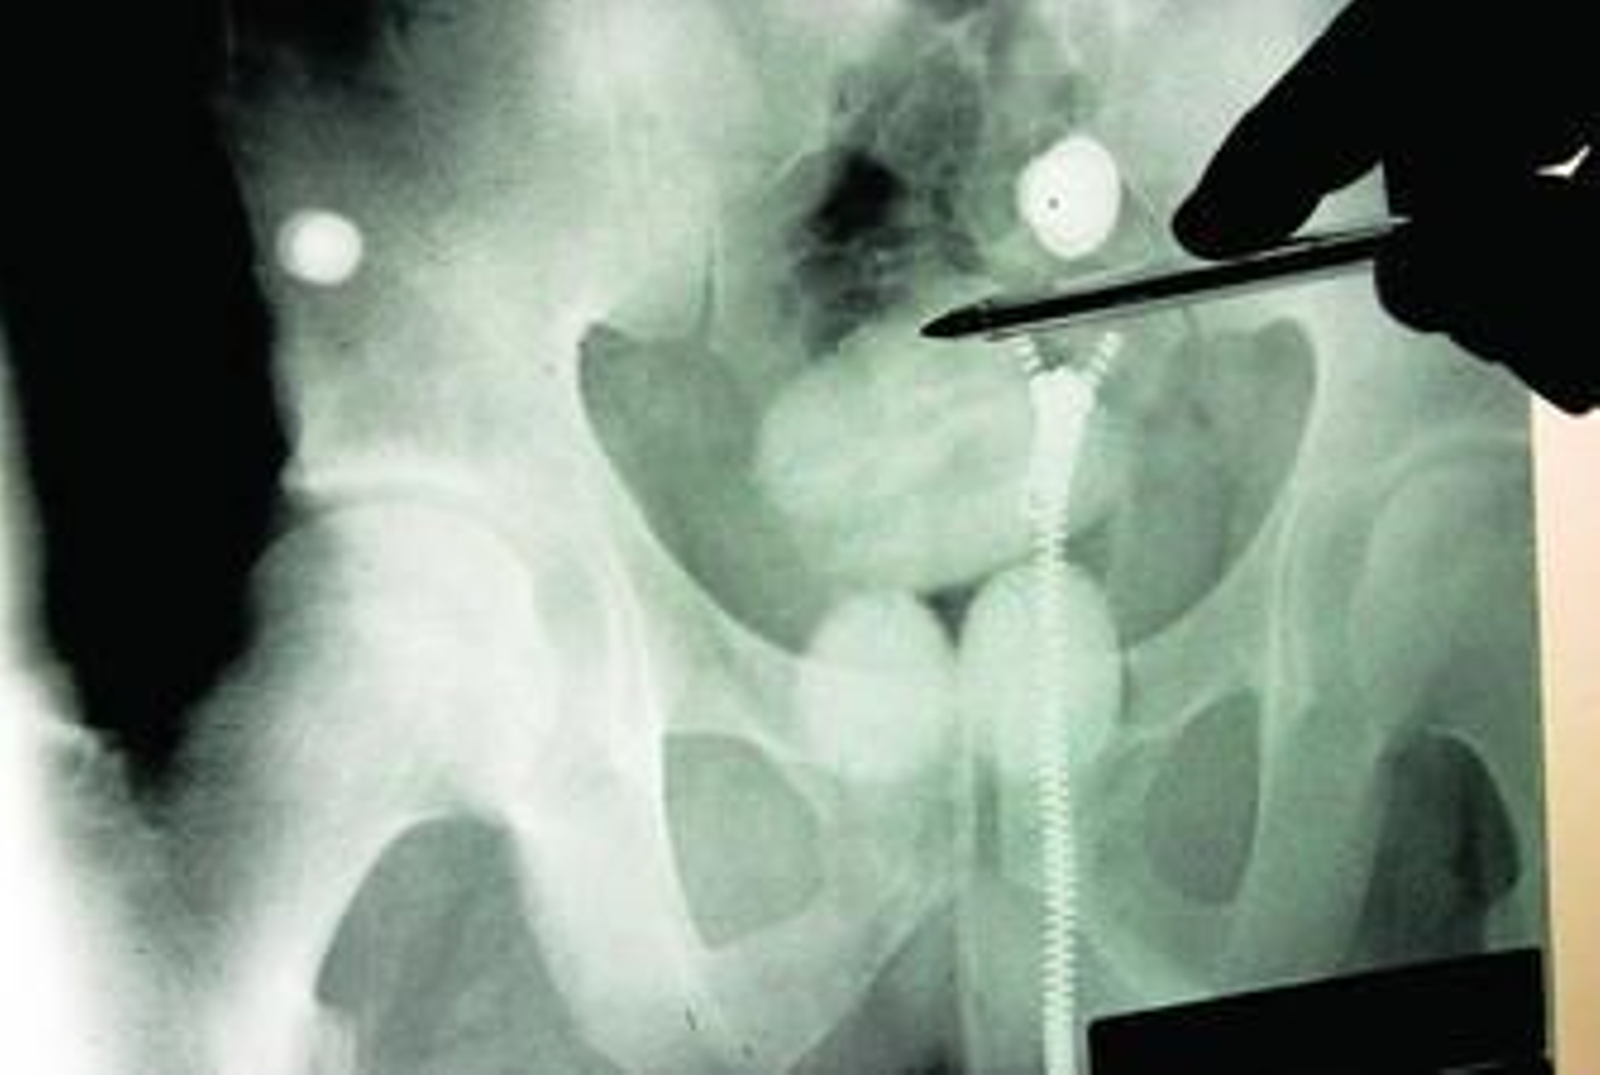

Otra radiografía en la que se comprueba un organismo repleto de pequeñas bellotas.

Las bellotas las ingieren ayudados por yogures y líquidos. Las hay de casi todos los tamaños. A los funcionarios del puerto les quedó grabado la sevillana que llevaba alojada en su vagina una bola de 1.275 gramos y a otro que escondía 180-200 bellotas, unos 2 kilos. La cocaína no se ve por esta frontera en cuerpos humanos.

Los transportistas que logran evadir los controles descargan y vuelven a sus andadas. A los que son sospechosos se los invita al reconocimiento. Primero se les cachea y luego son sometidos a una placa de rayos x. Si se negaran pasan a disposición judicial. La prueba médica se lleva a cabo en el mismo puerto, si no está operativo se traslada al hospital. En no más de diez minutos se conocen los resultados. Antes de 24 horas, la Guardia Civil da cuenta a la autoridad judicial y el sospechoso no puede estar detenido más de 72 horas. En este tiempo puede que no expulse todo y, por tanto, se avisa. Una nueva placa determina que ya está limpio. Otras veces los restos terminan de ver la luz cuando el individuo ya está en prisión.